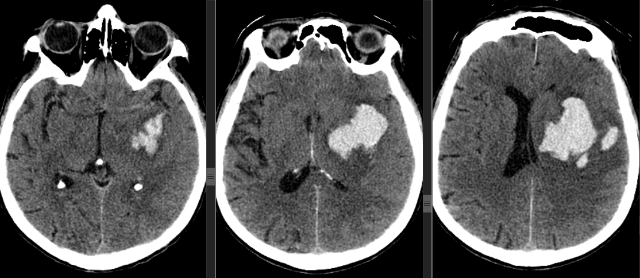

Инсульт удаление гематомы

Инсульт удаление гематомы 108 фотографий